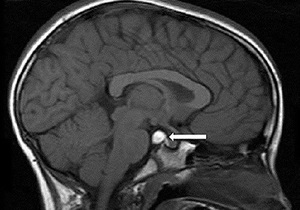

Пинеальная киста

Пинеальная киста головного мозга формируется в эпифизе — эндокринной железе, находящейся в области среднего мозга. Эпифиз также известен как шишковидное тело или пинеальная железа. Эта железа отвечает за выработку гормона мелатонина. При блокировке протока, по которому выделяется мелатонин, может возникнуть кистозное образование. Кроме того, к этому могут привести паразитарные инфекции мозга, такие как эхинококкоз.

Небольшая кистозная формация может не проявлять никаких симптомов. Однако, если её размер превышает 1 см, это может вызвать гидроцефалию и энцефалит. У пациента могут возникать головные боли, проблемы с координацией движений и двоение в глазах. Обычно маленькие кисты не требуют медицинского вмешательства, в то время как более крупные образования подлежат удалению хирургическим способом.